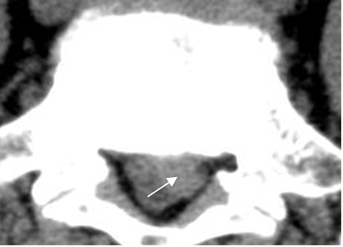

Fig 87. Hernia extruida.

A y B: RM sagital en T2. Protrusiones del disco, con desplazamiento inferior de los fragmentos.